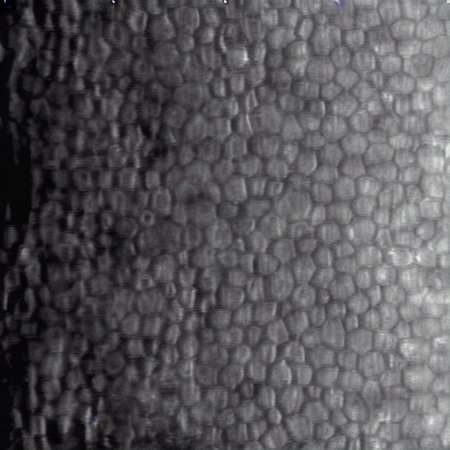

This LoRA generates photomicrographs of corneal endothelial cells in specular microscopy style (grayscale).

Normal Cells: Regular hexagonal honeycomb pattern.